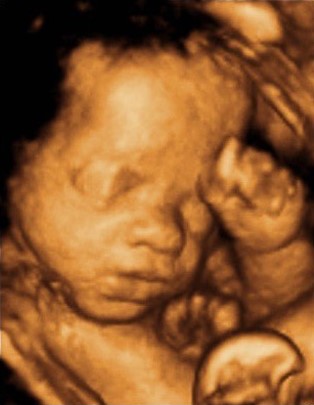

Transform ultrasound scans into photorealistic 3D models. TajseedAI's proprietary intelligence delivers unprecedented clarity from your most precious moments.

Watch flat ultrasound images become photorealistic, explorable 3D models in minutes.

TajseedAI's vision system analyzes structural data and generates a photorealistic synthetic output.

Our proprietary engine converts the output into a high-fidelity 3D model with realistic textures.